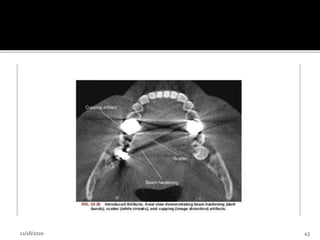

3.Introduced artifacts

 An x-ray beam pass through an object, lower energy

photons are absorbed in preference to higher energy

photons, this phenomenon is known as beam

hardening.

 Can result in 2 type of artifacts

1. Distortion of metallic structure as a result of

differential absorption, known as cupping artifact.

2. Streaks and dark bands, which when present

between 2 dense objects, create extinction or

missing value artifacts.

3.Introduced artifacts  Anx-ray beam pass through an object, lower energy photons are absorbed in preference to higher energy photons, this phenomenon is known as beam hardening.  Can result in 2 type of artifacts 1. Distortion of metallic structure as a result of differential absorption, known as cupping artifact. 2. Streaks and dark bands, which when present between 2 dense objects, create extinction or missing value artifacts. 12/18/2020 42